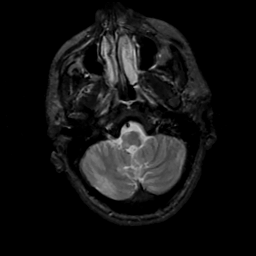

MR Study #5, March 10, 1991 -- Slice #9